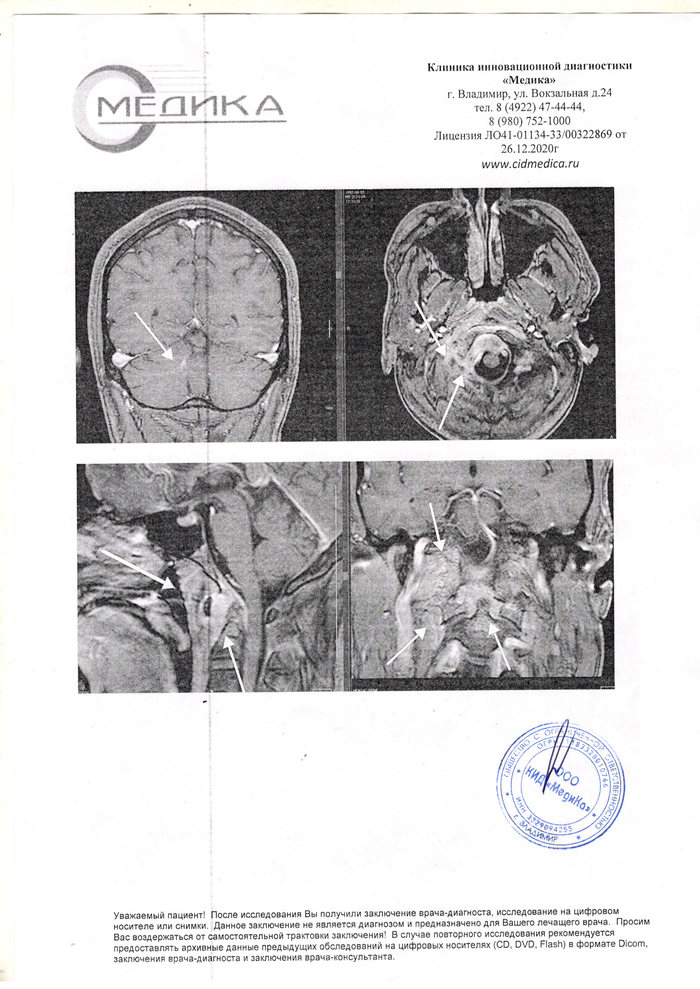

В результате падения с высоты собственного роста 24 Февраля 2024 потерял сознание,проснулся в больнице ,месяц лечили от ушиба и растяжении связок ШОП. При дальнейшем обследовании ( из-за очень сильных болей ) Выявили на Мрт,Мскт - Перелом второго шейного позвонка(?) и обсцесс в месте травмы. Неврологи,нейрохирурги,травматологи назначают лечение антибиотиками и обезболивающими на дому ..улучшений нет.Поворачивать головой право-лево, вверх-вниз не могу с самого начала и до сих пор. + Онемела правая часть затылка. Нейрохирург с стажем в 34 года сказал,что не видел таких случаев за свою практику никогда. Доктора отправляют из больницы в больницу. Из города в город..

Подскажите, пожалуйста, куда можно обратиться с такой проблемой, может быть кто-то сталкивался с таким ,как долго будет лечение?